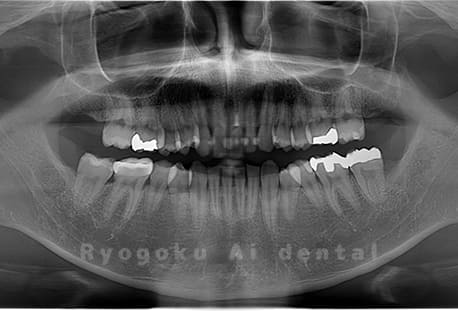

Case01

- 原因

- 水平埋伏智歯

- 治療内容

- 下顎の水平埋伏智歯を抜歯

<リスク・副作用>

手術後は痛み、腫れ、痺れなどの副作用が生じる場合があります。